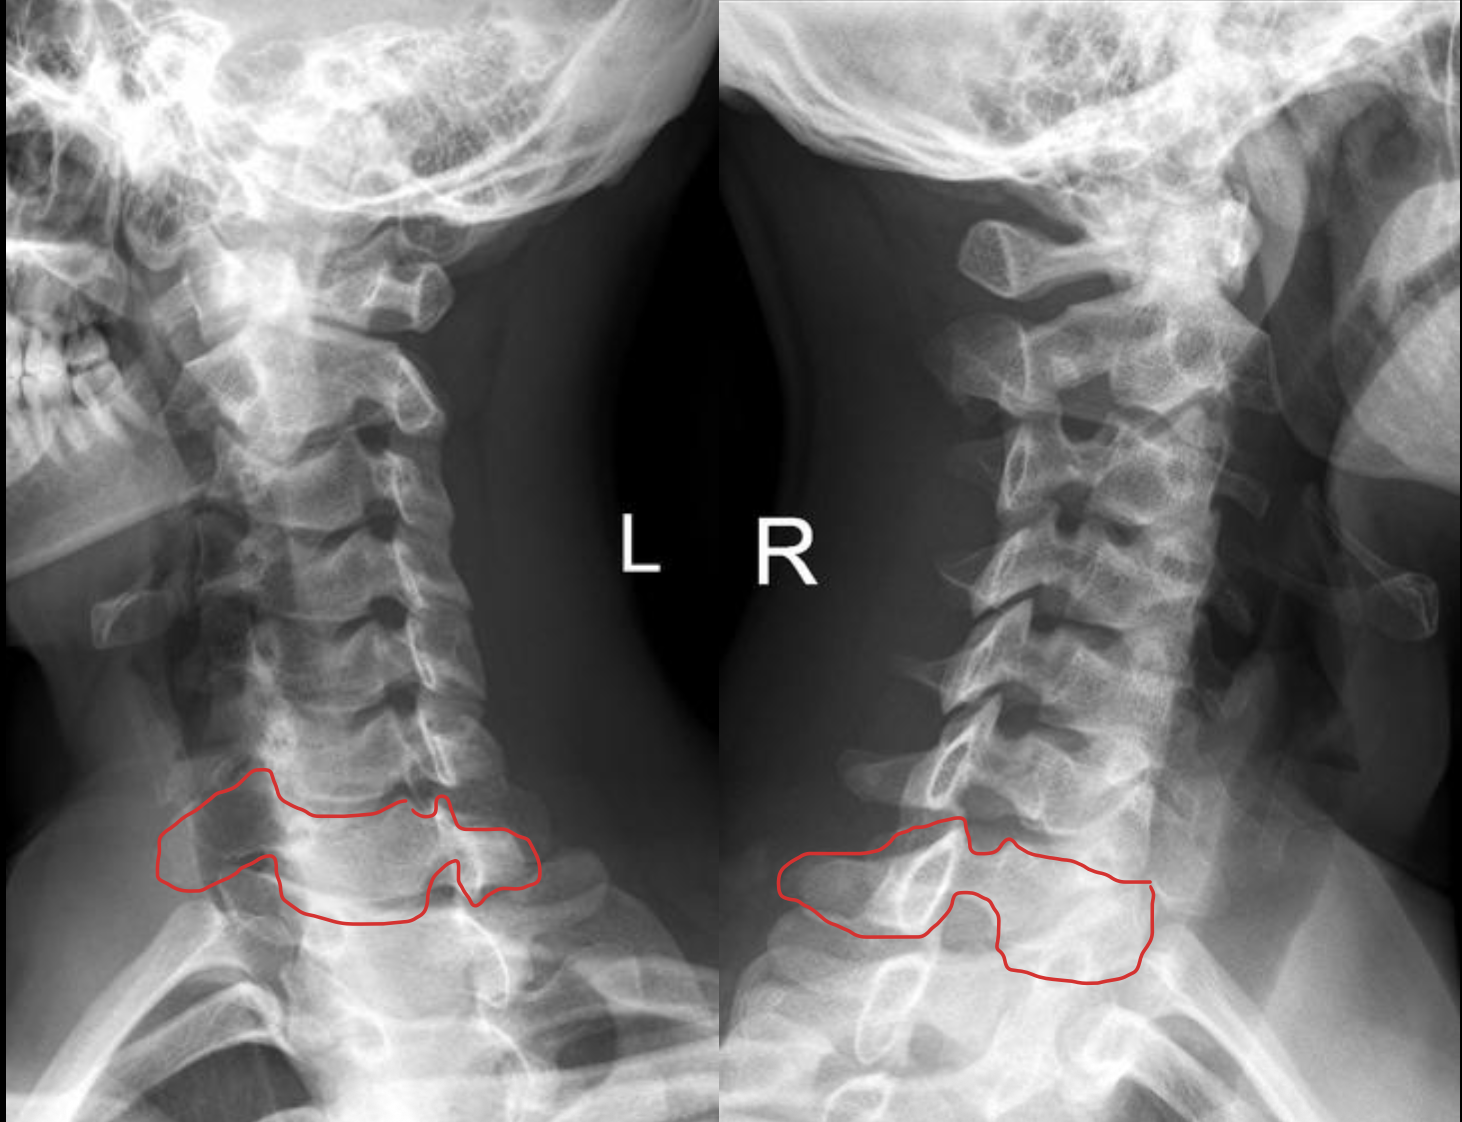

c6